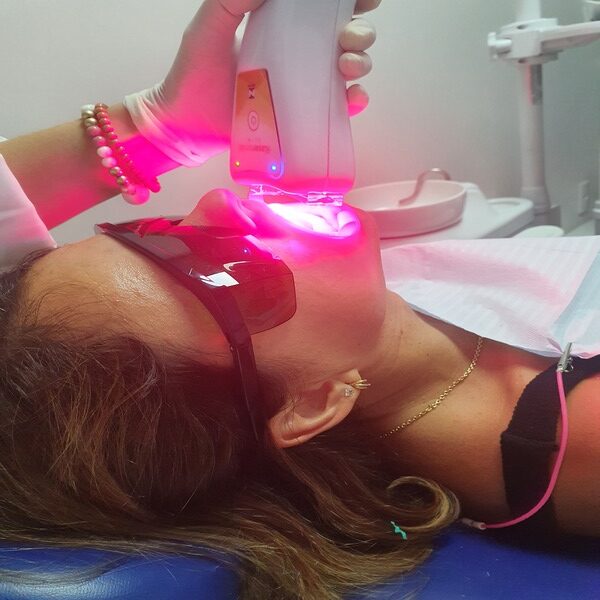

Habilitada em Laserterapia

Atuo nas áreas de clínica geral, dentística restauradora e estética, laserterapia com ênfase em dor na ATM (bruxismo, trismo), enxaqueca, sensibilidade dentária e lesões na mucosa oral. E, ledterapia para área de estética dental (clareamento) e pele (harmonização não invasiva).

Laserterapia